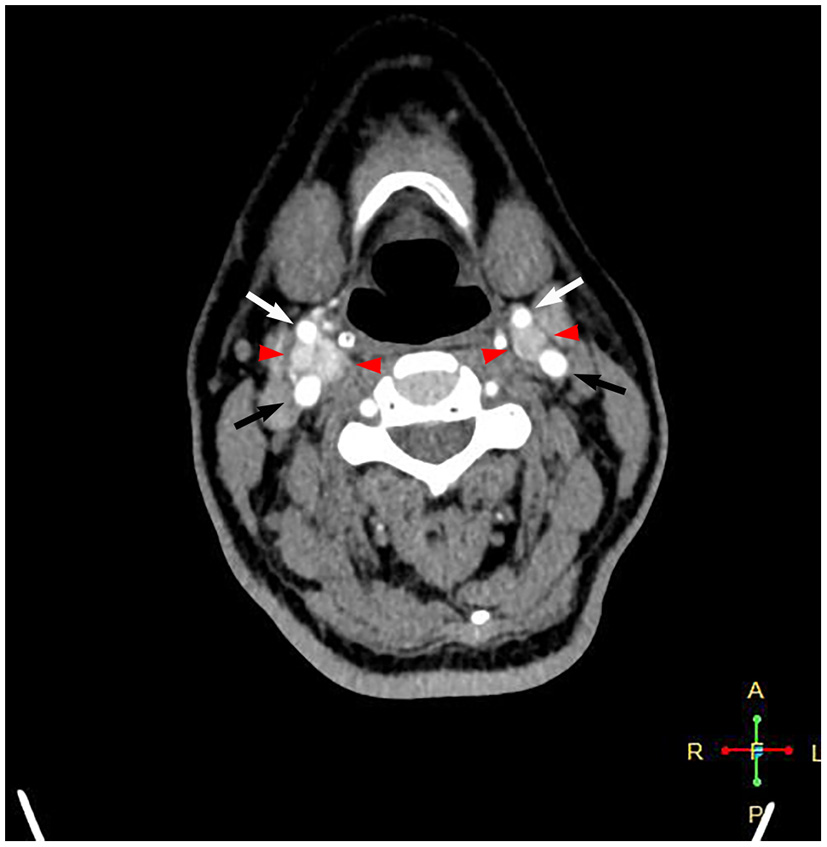

A 58-year-old female patient who was diagnosed with bilateral CBTs during a routine health check-up 3 years prior was admitted to the department of vascular surgery, Shanxi Provincial People's Hospital. She complained of a swelling sensation in her neck. The patient had no local pain, difficulty swallowing or breathing, voice changes, or palpitations. No systemic symptoms, such as fever, chills, and malaise, were present. There were no special records in her past medical history and family history. During a physical examination, a small, painless, firm, and pulseless mass was palpated on the right side of the neck at the carotid triangle located below the angle of the mandible. The Fontaine sign was positive. Physical examination did not reveal a left neck mass. The laboratory analyses did not suggest any other abnormalities, except slightly elevated low-density lipoprotein cholesterol and triglyceride levels. A routine electrocardiogram was normal. A computed tomographic angiography showed an intensely enhanced mass measuring 2.6 × 1.8 × 1.3 cm at the level of the right carotid bifurcation. A smaller mass measuring 1.1 × 0.9 × 0.9 cm was present on the left in a similar location (Figure 1). These findings were consistent with bilateral CBTs. According to the imaging results, the right tumor partially surrounded the carotid vessels, indicating Shambling II group tumor. The left-side tumor was of Shambling I group.

Figure 1

Computed tomography angiography showing intensely enhanced masses at the level of bilateral carotid bifurcations. Black arrows point to the internal carotid artery, white arrows point to the external carotid artery, and red arrowheads point to the carotid body tumor.